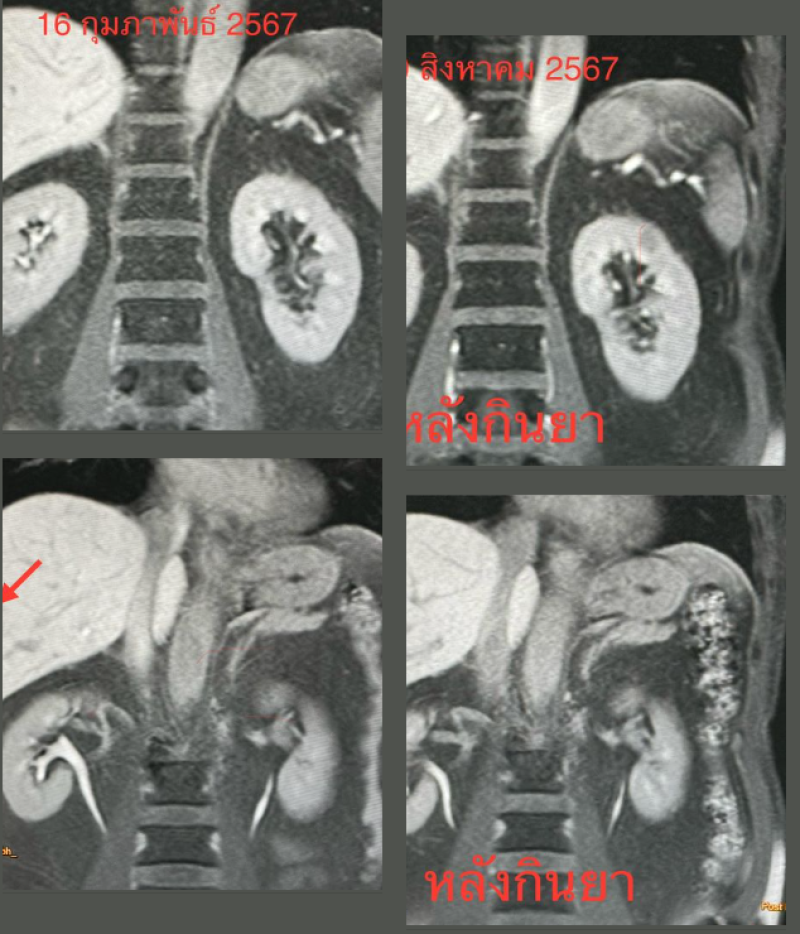

-ทำคลื่นแม่เหล็กไฟฟ้า MRI ของตับพบก้อนขนาด 2.8 × 2.4 × 2.1 ซม.และ 4.5 × 3.1 × 3.3 ซม.ในตับข้างขวา (ดูรูป)

ติดตามคนไข้ 6 เดือนหลังกินยาฆ่าพยาธิ วันที่ 19 สิงหาคม 2567 ไม่ปวดท้อง ไม่มีไข้ กินอาหารได้ เจาะเลือดพบจำนวนเม็ดเลือดขาว 5,620 เซลล์ เป็นเซลล์ชนิด eosinophil 8% (ลดลงเดิม 37%) ติดตามคลื่นแม่เหล็กไฟฟ้า MRI ของตับพบก้อนทั้ง 2 ก้อนในตับข้างขวาขนาดเล็กลงมาก